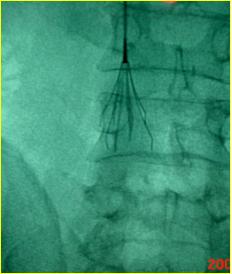

急诊造影:小腿深静脉通畅,腘静脉通畅,见图2

图2